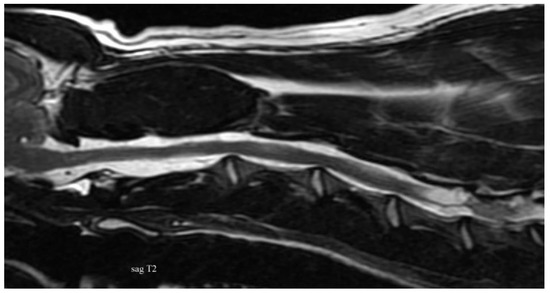

3.2. Diagnostic Imaging